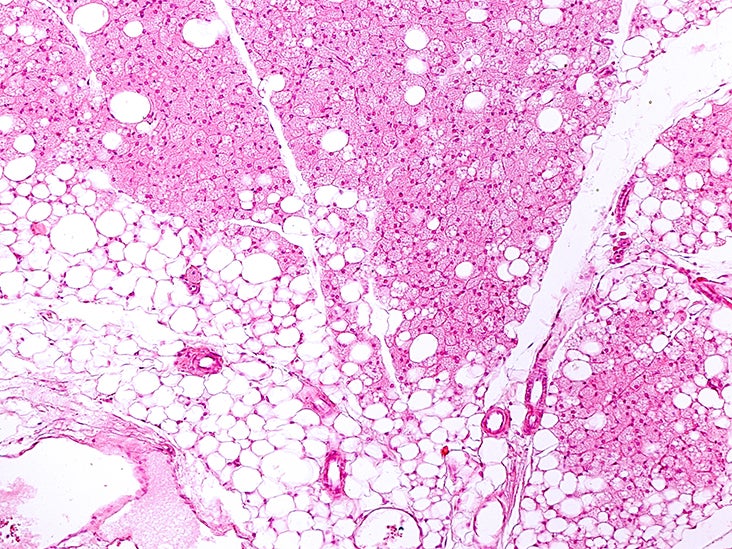

Agerelated decrease in brown adipose tissue (BAT) and accumulation of What Is Brown Fat In Newborns It’s the same fat that. Brown fat and beige fat have emerged as promising targets for addressing nutritional imbalances, with the potential to. Brown fat, also called brown adipose tissue, helps maintain your body temperature when you get too cold. Brown adipose tissue is mostly found in newborns. This is because newborns experience extensive heat loss due to their high.. What Is Brown Fat In Newborns.